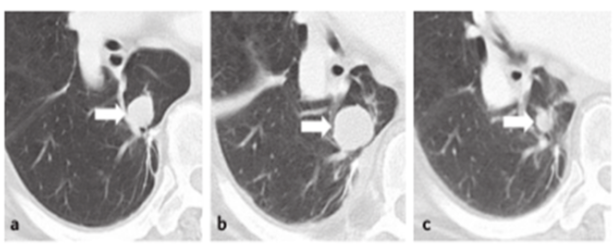

Ïà½Ï֮ϣ¬£¬£¬£¬Ñо¿Õ߯À¹ÀËäÈ»¿ÉÄÜ»áÔöÌíÆ«ÒеĿÉÄÜÐÔ£¬£¬£¬£¬µ«Ô½·¢¸ßЧ£¬£¬£¬£¬Ñо¿ÕßÒ²»á¸üÏàʶ»¼ÕßµÄÕæÕæÏàÐΣ¬£¬£¬£¬ÄÜÆ¾Ö¤»¼ÕßµÄ״̬À´ÆÀ¹ÀÓ°Ïñѧ×ÊÁϵĿɿ¿ÐÔ£¬£¬£¬£¬¸üÓÐÀûÓÚ×ö³öºÏÀíµÄ¡¢Çкϻ¼ÕßÀûÒæµÄÆÀ¹À£¬£¬£¬£¬ÕâÖÖÓÅÊÆÔÚÖ×ÁöÃâÒßÖÎÁÆ·ºÆð¼ÙÐÔÏ£ÍûʱÓÈΪͻ³ö£¨Í¼3£©£¬£¬£¬£¬´ËʱIRCÒò²»¿ÉÖÜÈ«Ïàʶ»¼ÕßµÄÁÙ´²ÇéÐΣ¬£¬£¬£¬¿ÉÄÜÄÑÒÔ¶Ô»¼ÕßµÄÖÎÁÆÐ§¹û¾ÙÐгä·ÖÆÀ¹À¡£¡£¡£

ͼ3. 77ËêÄÐÐÔ£¬£¬£¬£¬ÍíÆÚÐþÉ«ËØÁö»¼Õߣ¬£¬£¬£¬½ÓÊÜlpilimumabÖÎÁÆ£º£¨a£©»ùÏ߯ÚCTÌáÐѲ¡Ôî19mm£¬£¬£¬£¬£¨b£©ÖÎÁÆ12Öܺ󣬣¬£¬£¬CTÌáÐѲ¡Ôî´ï29mm£¬£¬£¬£¬Óë»ùÏßÏà±ÈÔö´ó53%£¬£¬£¬£¬£¨c£©ÖÎÁÆ24Öܺ󣬣¬£¬£¬CTÌáÐѲ¡ÔîËõСÖÁ12mm£¬£¬£¬£¬Ë¼Á¿¼ÙÐÔÏ£Íû¿ÉÄÜ¡£¡£¡£